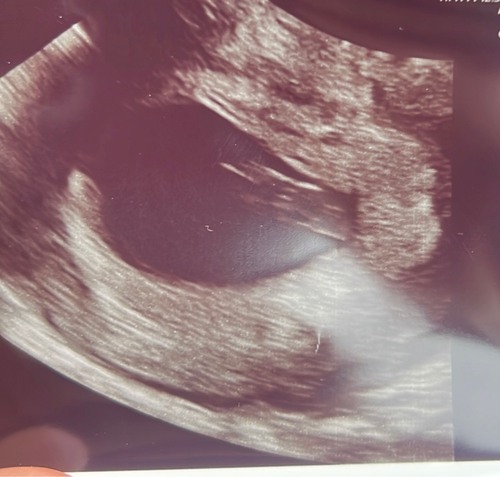

Gisteren 31-10 met 7+3 weken een uitwendige echo 😍